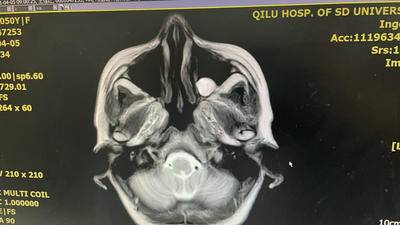

点赞(0) 举报核磁检查显示脑膜多发转移,找到腿疼原因了,